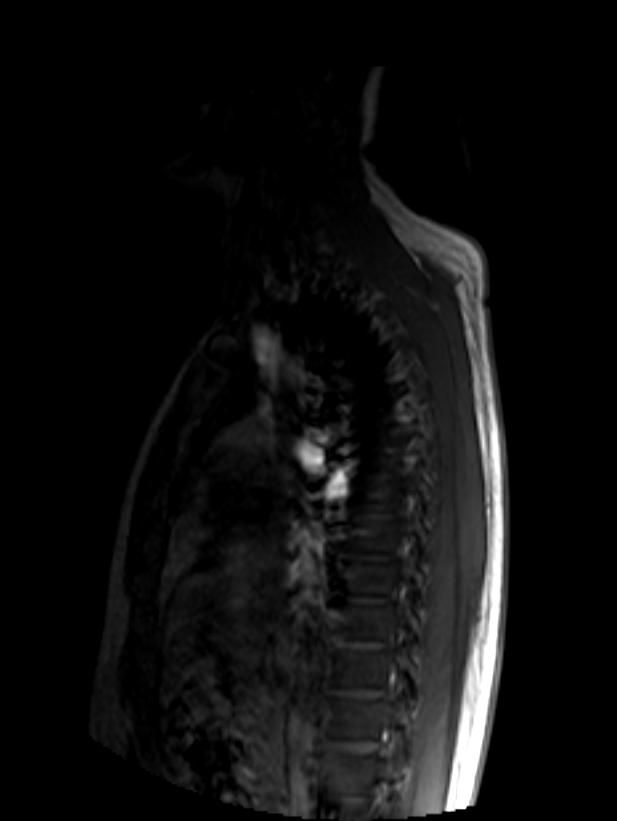

• 우선 이 영상은 T2 강조 시상면(sagittal) MRI 영상으로 보이며, 전체 척추를 한 번에 촬영한 전척추(whole spine) 스크리닝 영상으로 판단됩니다.

말씀하신 "상체 부분 중간의 하얀 음영"은 흉추(thoracic spine) 부위에서 보이는 T2 고신호(high signal intensity) 병변으로 보입니다. T2 영상에서 밝게 보인다는 것은 해당 부위에 수분 함량이 높은 조직이 있다는 의미인데, 이것이 곧 악성 병변을 의미하지는 않습니다.

가능한 감별 진단을 말씀드리면, 우선 가장 흔한 원인은 추간판(intervertebral disc) 내의 수분 변화 혹은 Schmorl's node처럼 양성 구조적 변화입니다. 그 외에 혈관종(vertebral hemangioma)은 척추에서 매우 흔하게 발견되는 양성 종양으로, T2에서 밝게 보이는 전형적인 소견을 보입니다. 척추 혈관종은 성인의 10퍼센트 이상에서 우연히 발견될 만큼 흔하며 대부분 치료가 필요 없습니다.

물론 영상 한 장만으로 확정적인 판독은 어렵고, 전체 시퀀스(T1, T2, 조영증강 여부 등)와 임상 증상을 함께 고려해야 정확한 판단이 가능합니다.